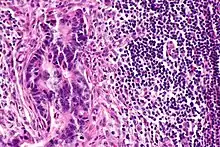

![]() | Squamous cell carcinoma of cervix | Invasive Squamous Carcinoma of the Cervix. Cold Knife Cone. | Category: Histopathology of squamous cell carcinoma of the cervix | Invasive squamous carcinoma of cervix |